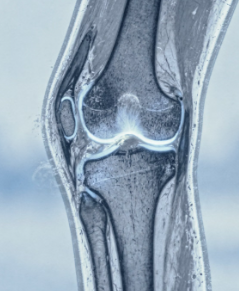

7. 관절염

관절염이 있는 경우 연골이 손상되면서 관절 마찰이 증가할 수 있습니다.

이 경우 소리와 함께 통증, 붓기, 뻣뻣함이 나타날 수 있습니다.